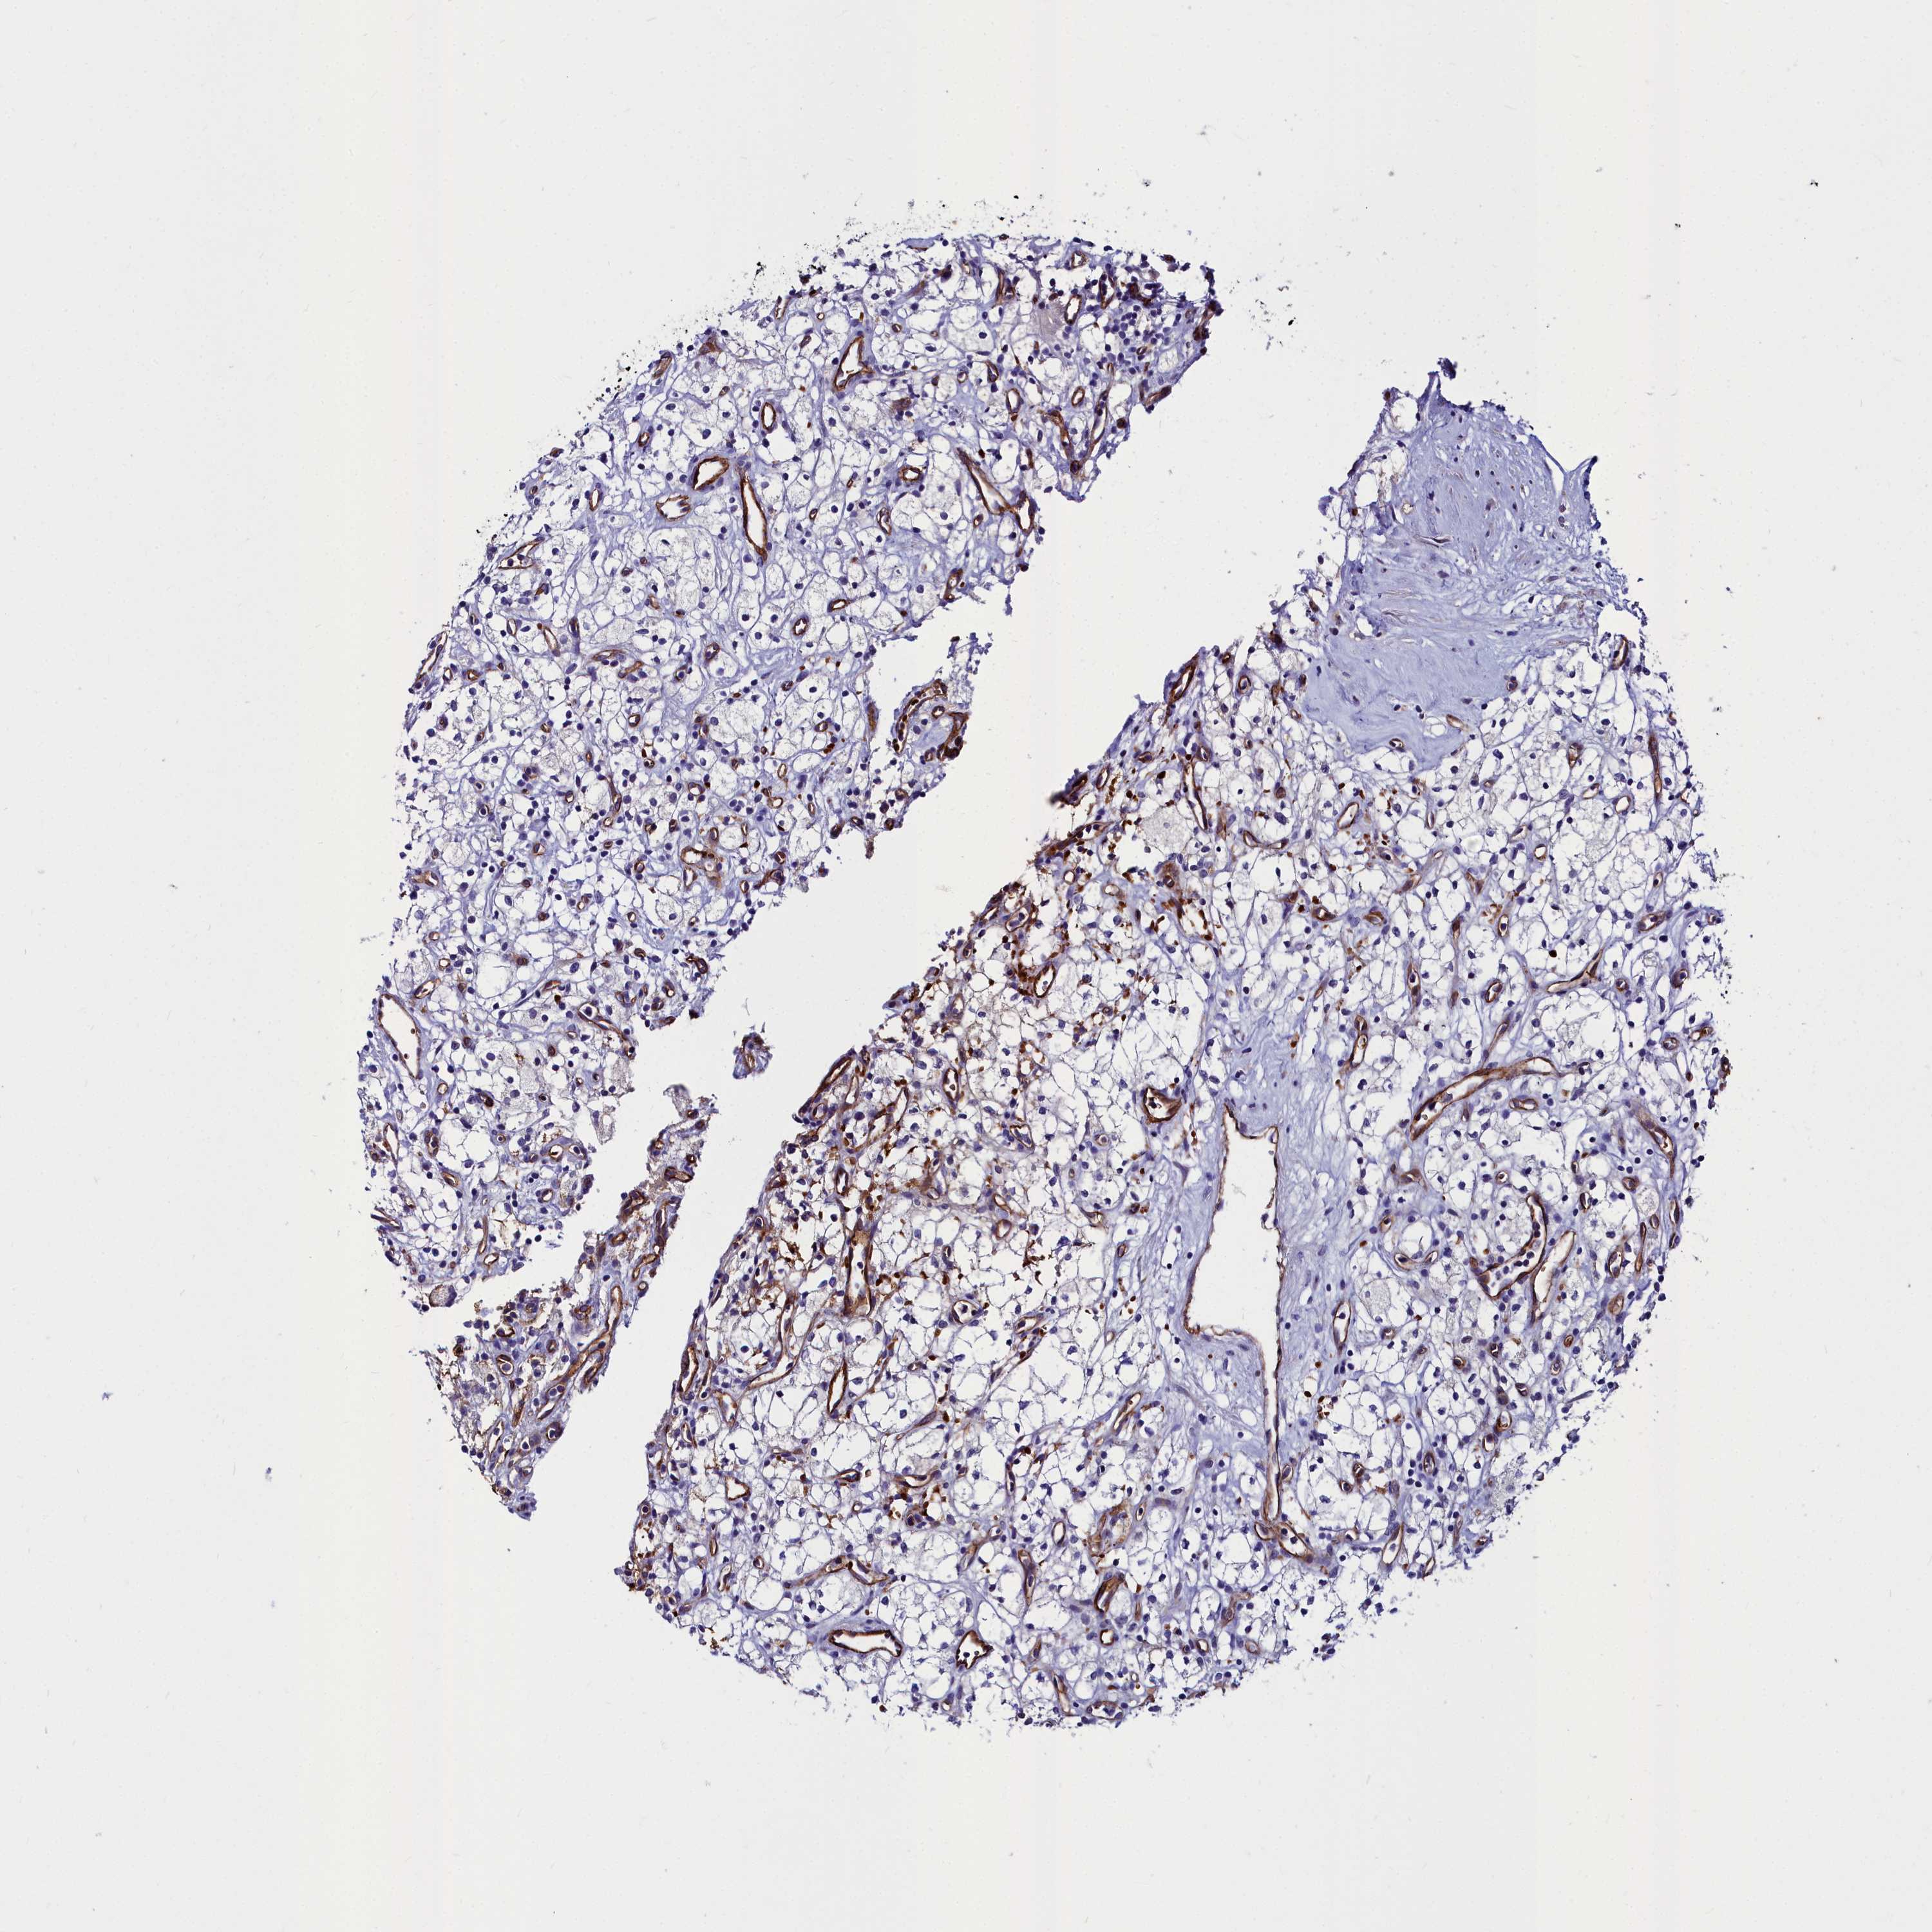

CANCER RENAL CANCER Show tissue menu

KICH TCGA KIRC TCGA KIRC VALIDATION KIRP TCGA PROTEIN RCC CPTAC PROTEIN EXPRESSION